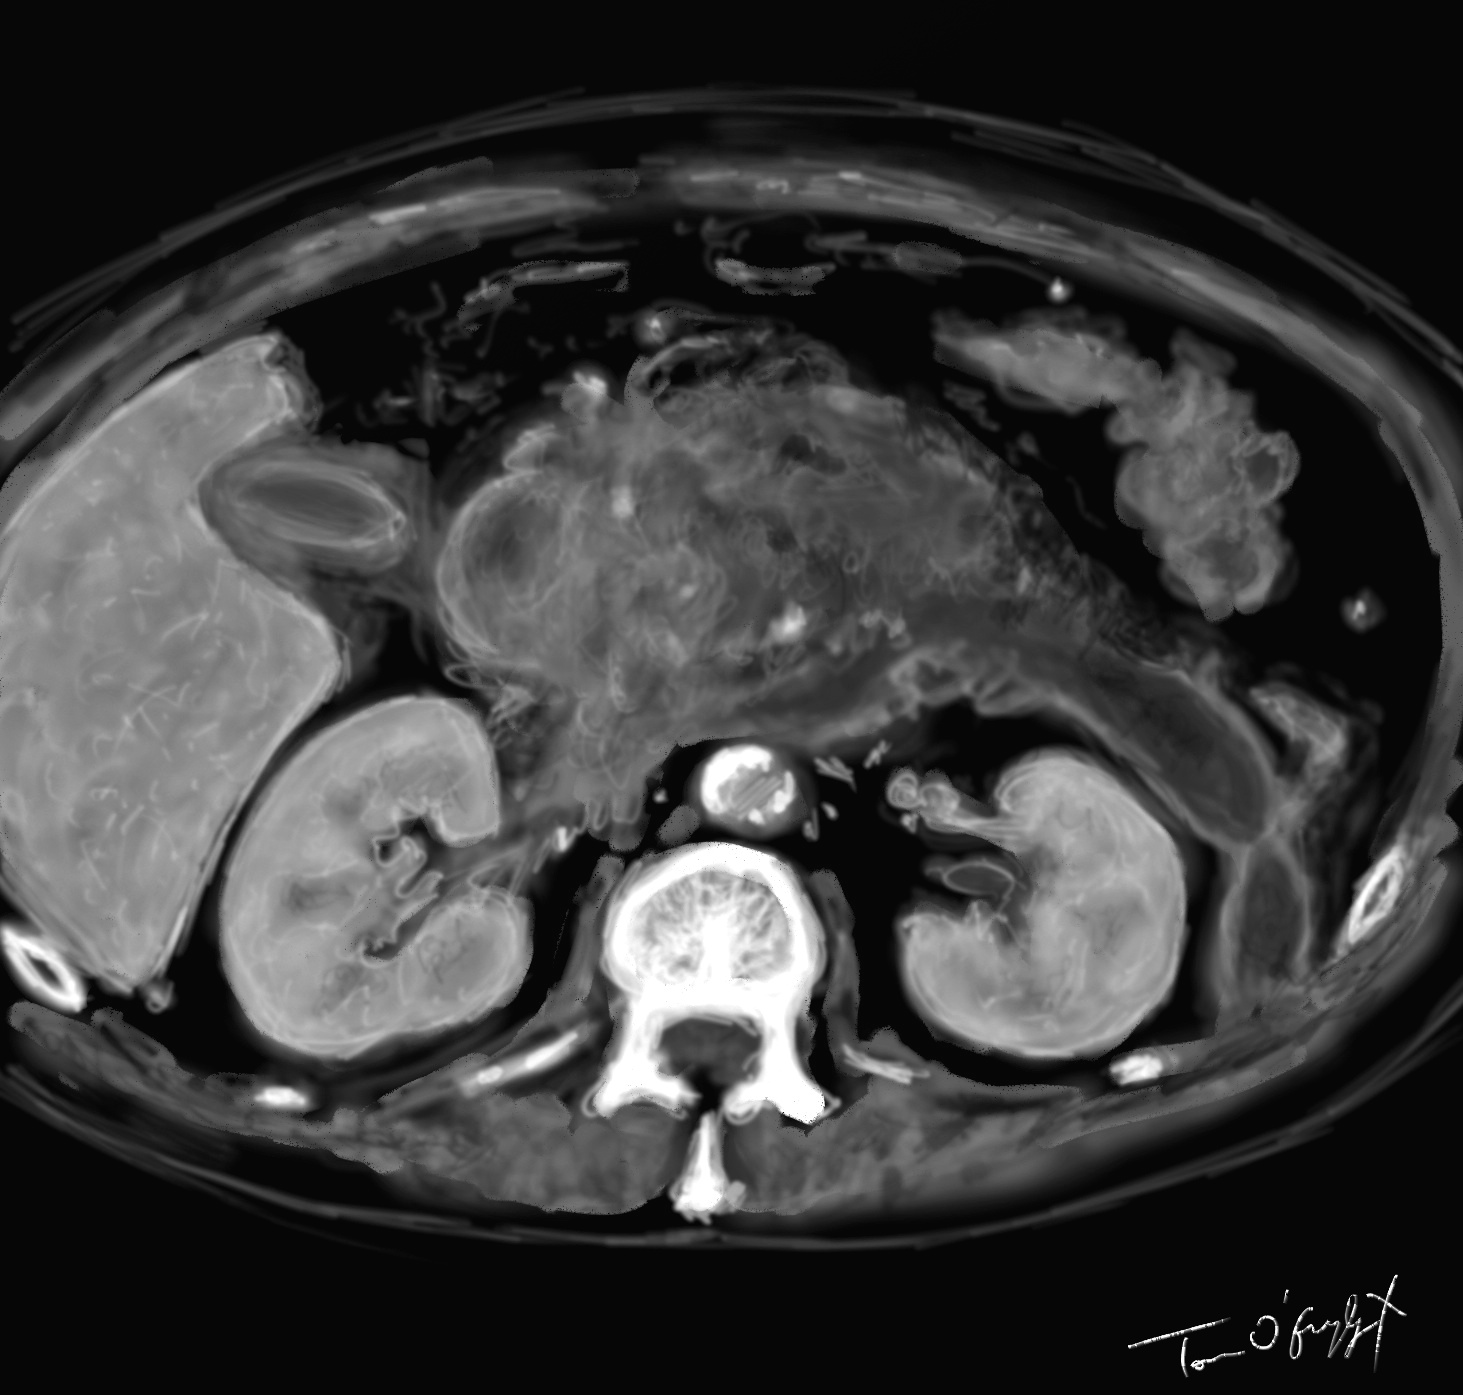

scanner de pancréatite aiguë nécrosante stade E avec importante réaction oedémateuse et coulée de nécrose

Le scanner est devenu la pierre angulaire de la prise en charge diagnostique de la gravité et des complications, mais il n’est pas exempt de défauts. La conférence de consensus de 2001 réactualisée considère que la TDM n’est pas à réaliser en urgence si le diagnostic est fait sur des critères cliniques et biologiques. Au mieux réalisée à J3, elle permet par l’utilisation de la classification de Balthazar d’établir un pronostic sur l’évolution. Les recommandations repoussent même encore au-delà les indications, à savoir pas de scan sur une pancréatite aiguë de gravité faible (car évolution favorable en 72h), et de le réserver à partir de gravité intermédiaire et élevée. Elles conseillent la réalisation dans les 5 à 7 jours d’évolution ou dès le départ quand il y a un doute diagnostique. Certaines images d’infiltration liquidienne à la phase initiale peuvent en imposer pour des images de nécrose, alors qu’elles vont régresser après quelques jours, surévaluant la gravité de la PA.

Le score scanographique de Balthazar classe en 5 stades l’évolutivité :

L’évaluation de la taille de nécrose (0 : défaut de rehaussement du parenchyme, < 30 %, 30-50 %, > 50 %) compte aussi.